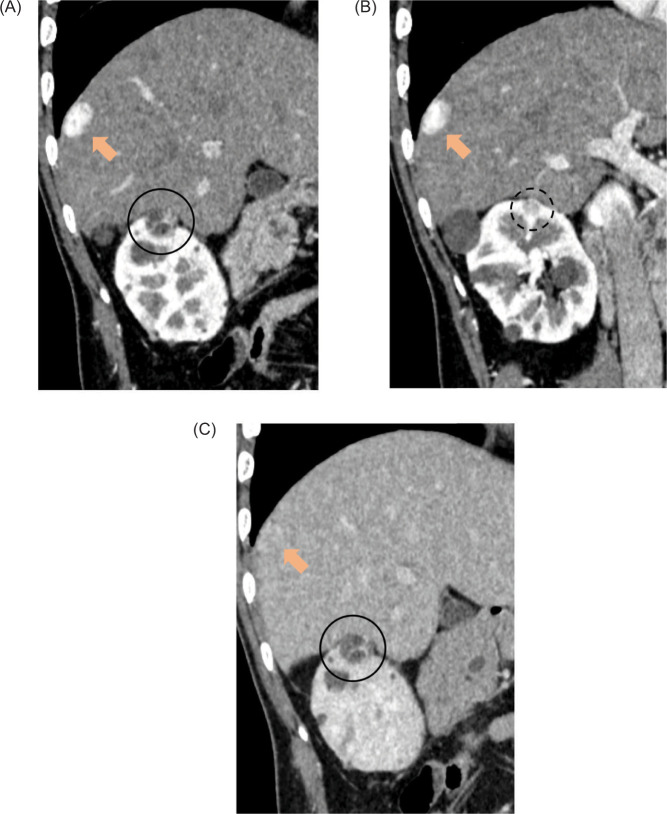

我们报告了一名 38 岁男性的病例,他患有两个与冯-希佩尔-林道病相关的 T1a 肾细胞癌(RCC)(见图 1)。

We report the case of a 38-year-old man with two von Hippel-Lindau disease-associated T1a renal cell carcinomas (RCCs) (<2 cm in diameter) which developed into a 2.5-cm solitary diaphragmatic metastatic tumor. After diagnosis using percutaneous biopsy, the diaphragmatic metastasis and two RCCs were treated by laparoscopic resection and percutaneous cryoablation, respectively. One year after treatment, the patient survived without local recurrence or distant metastasis. This report describes a rare case of RCC metastasis in VHL disease and its treatment.